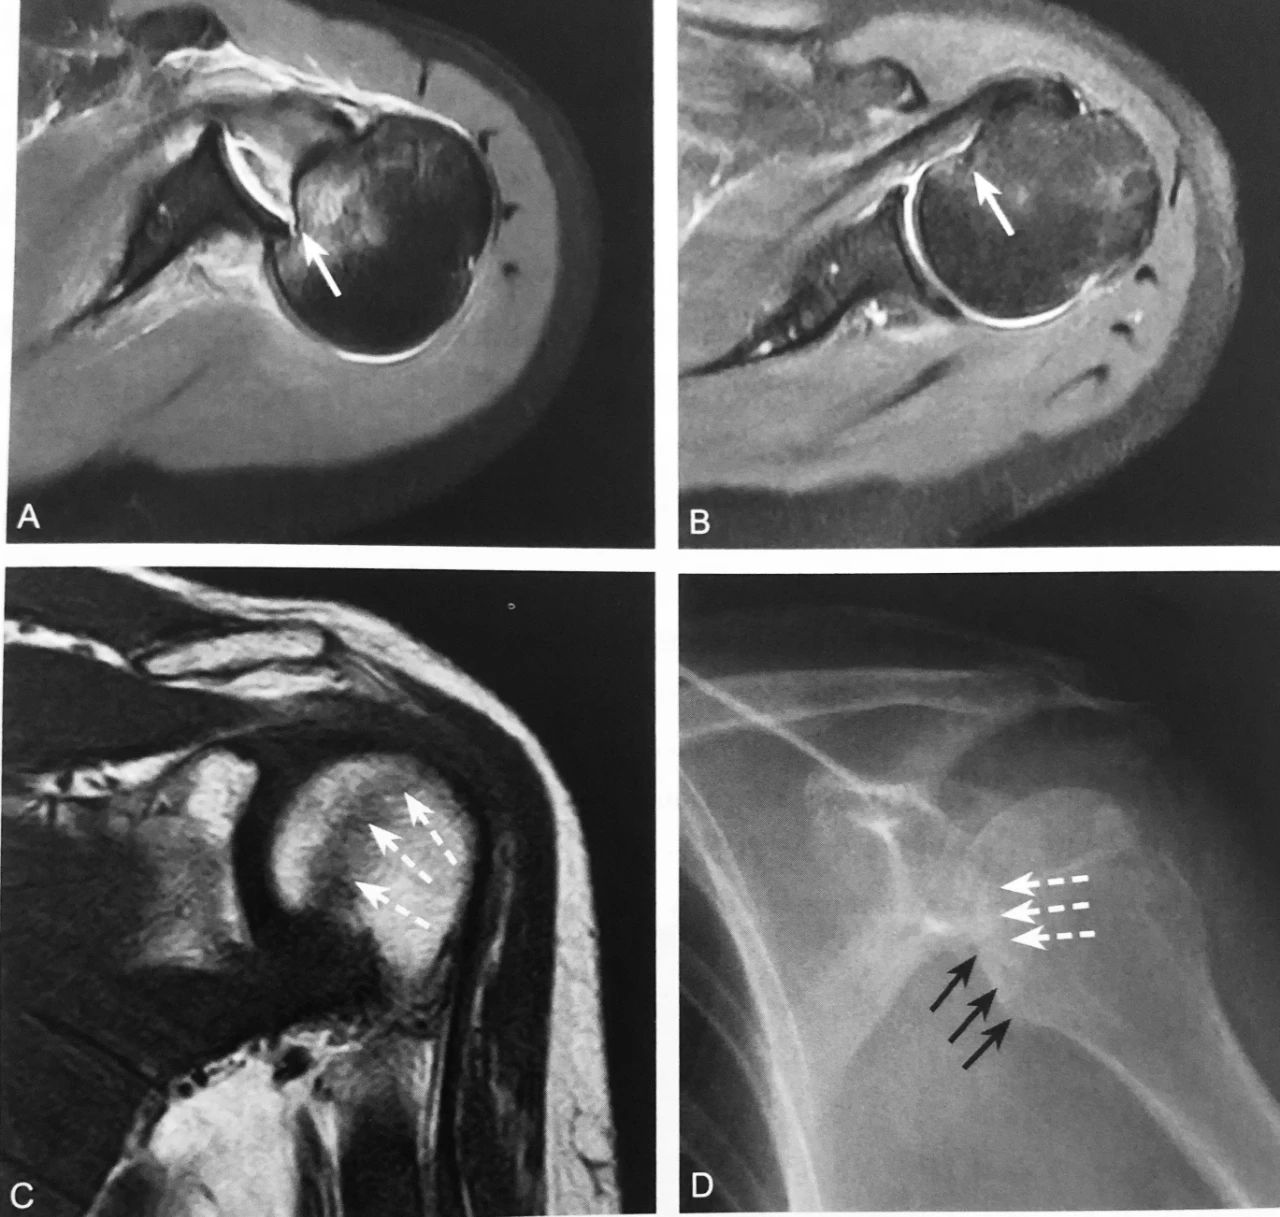

凹槽线:A~D 图为左肩关节后脱位的一位患者。A.左肩关节 MRI 横断位 T2WI 示:肱骨头内旋并嵌顿于关节盂后方,肱骨头前内侧凹槽样压缩骨折(白实箭头),并邻近骨髓水肿;B.左肩关节 MRI 横断位 T2WI 示:盂肱关节复位后肱骨头凹槽样形态仍存在(白实箭头);C.左肩关节 MRI 斜冠状位 T1WI 示:复位后肱骨头前内侧条形低信号影(白虚箭头)存在,提示撞击后损伤改变;D.左肩前后位 X 线示:肱骨头内侧皮质线形态(黑实箭头)和内侧皮质线外侧的凹槽线样改变(白虚箭头)

判读要点:

1、肩关节后脱位并肱骨头压缩性骨折的间接征象;

2、在肩关节 X 线前后位片观察;

3、X 线腋位摄片显示更清楚,对明确诊断很有帮助。